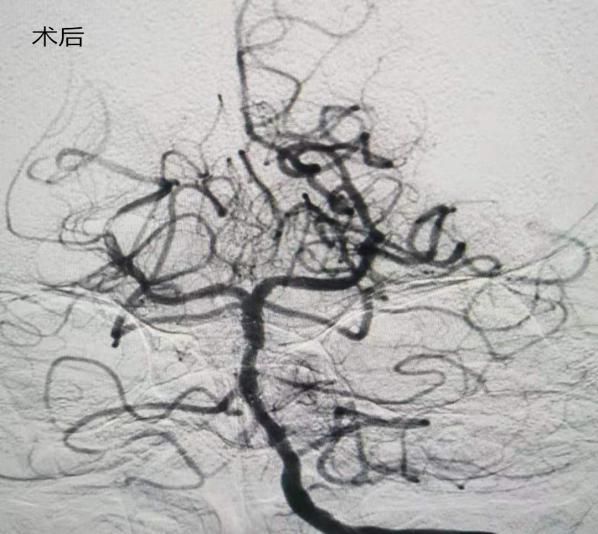

(1)2018年11月1日开展第一例主动脉弓并脑血管造影。

患者:王某 男性  41岁  城关镇

术前

术后